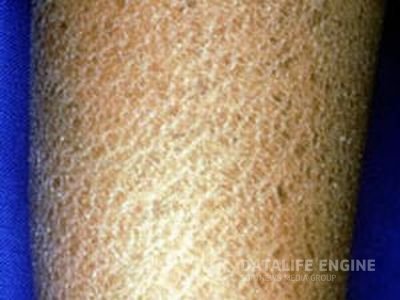

Ихтиоз («рыбья чешуя»)При ихтиозе кожа становится очень сухой и шелушится, что дало повод назвать это заболевание «рыбьей чешуей».... Ихтиоз («рыбья чешуя»)При ихтиозе кожа становится очень сухой и шелушится, что дало повод назвать это заболевание «рыбьей чешуей»....